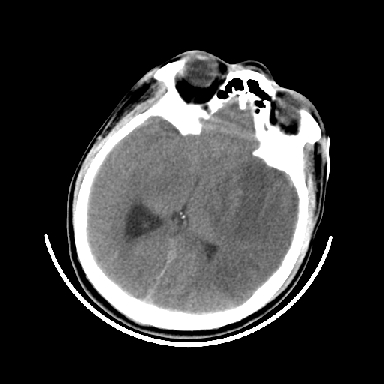

以下是引用dyqct在2007-4-9 11:18:00的发言:[br]左额颞顶叶、基底节区呈大片低密度区,累及皮质,中度占位效应,同侧侧脑室旁见小片状高密度区,边界清楚。中线结构向右弧形移位。右侧侧脑室略扩张。[br]考虑:1、左侧额颞顶叶、基底节区缺血性脑梗塞(符合大脑中动脉供血区)伴出血。[br] 2、建议增强扫描进一步检查。

以下是引用卜一在2007-4-9 15:08:00的发言:[br][br] 左侧额颞顶叶、基底节区缺血性脑梗塞(符合大脑中动脉供血区)伴出血。原因:多考虑外伤后出血,形成血栓所致。 [br]